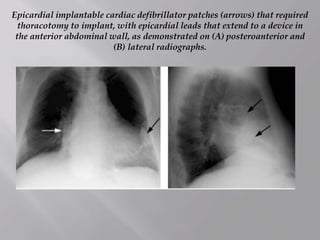

Epicardial implantable cardiac defibrillator patches (arrows) that required

thoracotomy to implant, with epicardial leads that extend to a device in

the anterior abdominal wall, as demonstrated on (A) posteroanterior and

(B) lateral radiographs.